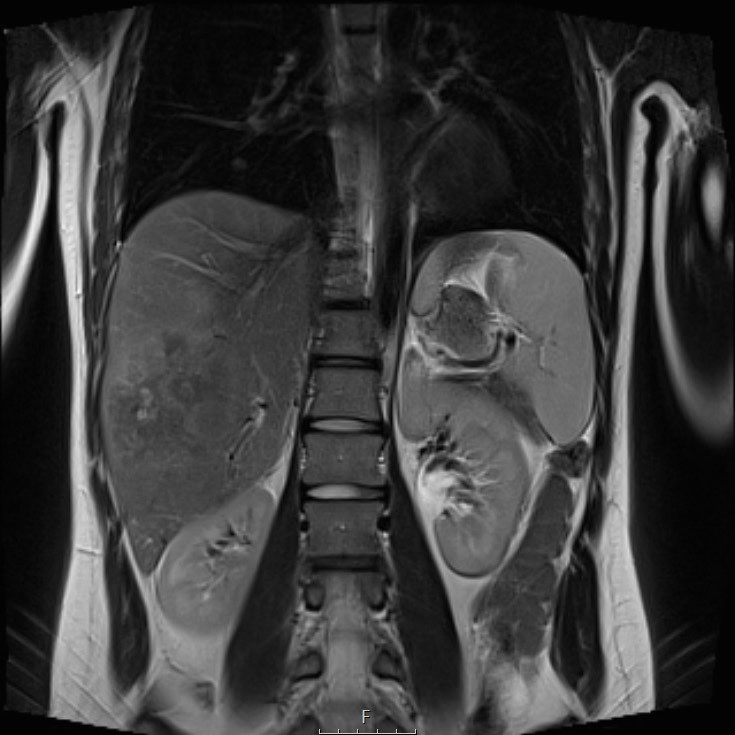

Ví dụ 1

Một bé gái 17 tuổi nhập viện với triệu chứng đau bụng vùng thượng vị. Siêu âm phát hiện một khối u gan lớn.

Trên MRI thấy khối u ở phân thùy gan 5 và 6 với các tổn thương vệ tinh ở phân thùy 7 và 8 (mũi tên). Có huyết khối u trong tĩnh mạch cửa phải (đầu mũi tên) và nhiều di căn phổi (*).